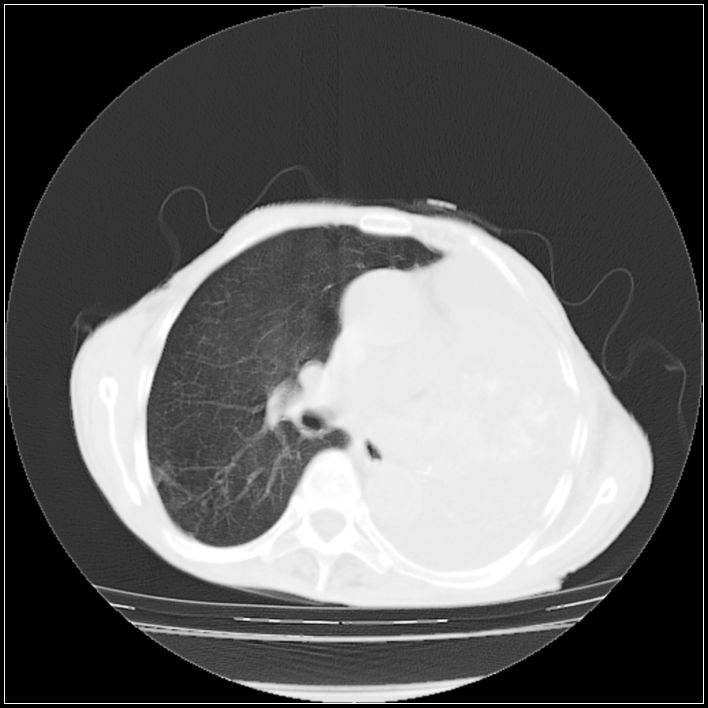

以下是引用ydx_74在2008-5-31 16:08:00的发言:[br]中心性肺癌并左侧肺不张、胸水。

以下是引用影象小辈在2008-5-31 16:25:00的发言:[br]左侧胸腔团状不规则致密影,界欠规整,密度不均匀,其内可见更低密度影及高密度影,并可见包裹性胸腔积液 考虑为1.畸胎瘤 2.肺癌